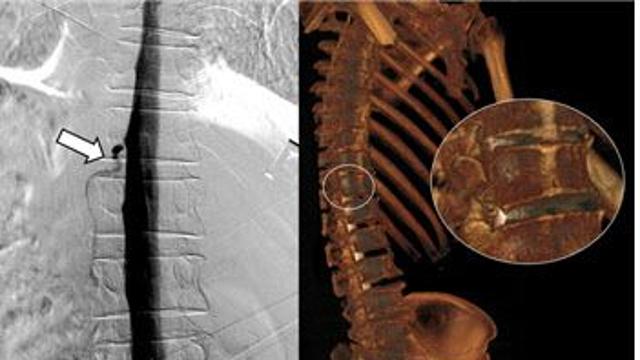

일교차 큰 가을, 허리는 안녕하신지요?

메디먼트뉴스 2025.10.15

"허리뼈가 '볼록' 앞으로 굽었네요"…척추전만증, 아세요?

모두서치 2025.10.15